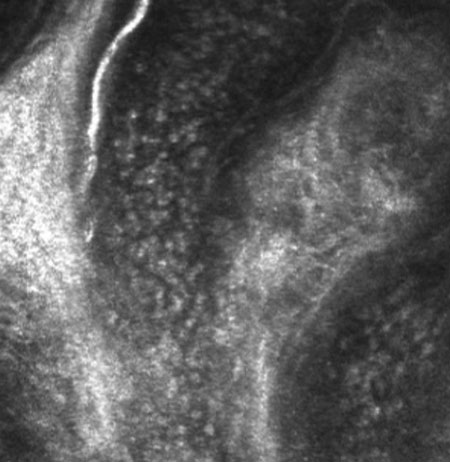

Figure 4.

Representative movie of rapidly moving blood cells within a vessel of a normal subject. Note the lack of rolling and arrested leukocytes in comparison to the patient with scleritis (Figure 2).

Note that the slide bar at the bottom of the quicktime movie can be used to manually control the flow of the movie. If you are unable to view the movie, a representative frame is included below.